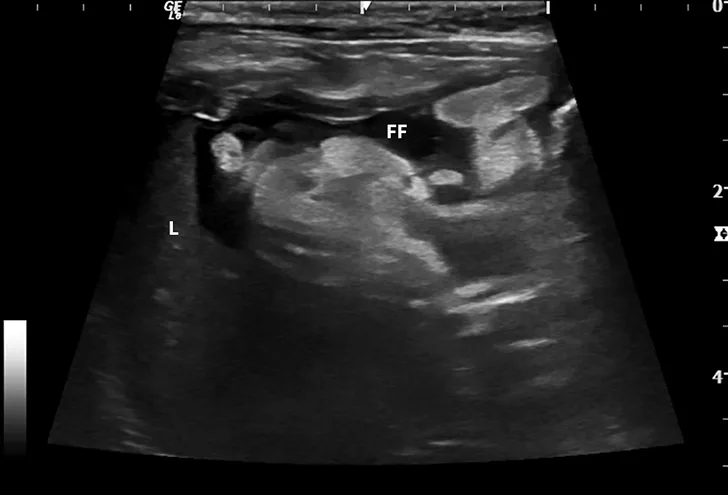

Dry FIP can manifest with organ dysfunction, uveitis, neurologic signs, fever, anemia, and/or lethargy and is caused by granulomas or immune complex deposition. Cats with wet FIP may have ascites or pleural effusion in addition to the aforementioned signs (Figure 1). Clinical presentation can vary from minor to life-threatening and involve almost any organ system.

Abdominal ultrasound images from a cat.

FIGURE 1

Ultrasound image showing abdominal effusion in a cat with wet FIP. Anechoic fluid is present between organs, distending the abdomen. FF = free fluid; L = liver; S = spleen; K = kidney